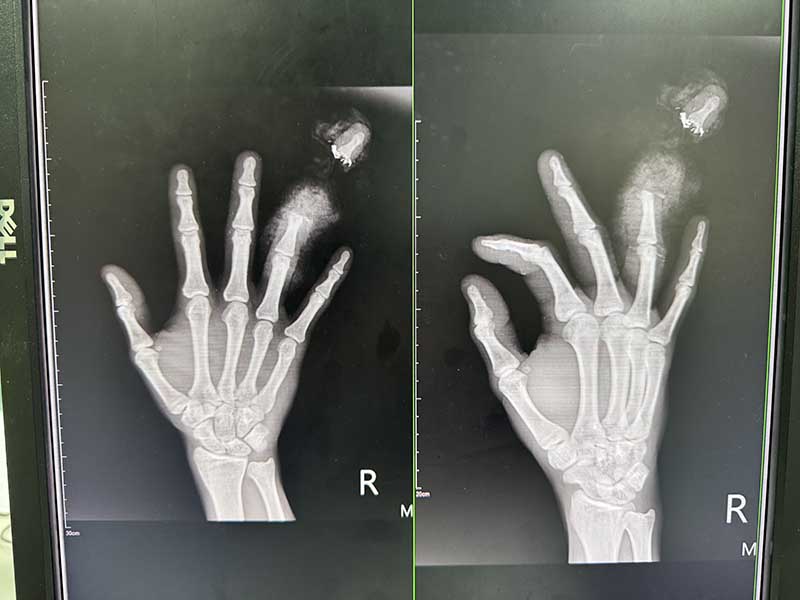

烏日林新醫院整形外科魏經岳主任表示,斷指是否能成功重接,關鍵在於傷口的嚴重程度、缺血時間、患者年紀、身體狀況與即時處理的品質。顯微手術的主要目的在於讓斷指能夠恢復功能,在進行顯微斷指重接血管縫合手術前,必須先把受損組織進行清創,保留正常組織後,再重新釘好切斷的指骨以及修復甲床,最後藉由高階顯微鏡放大倍率,進行難度高的血管及神經接合,過程必須全神專注且相當精準才能順利縫合血管。所幸最後在手術經驗豐富的整形外科魏經岳主任細心處置下,及時搶救順利接回!

針對顯微斷指重接血管縫合手術的術後護理,傷口部位若是顏色變黑、異味或是出血,避免手指腫脹壞死,必須立即回診。另外整形外科魏經岳主任也提醒阿里術後避免抽菸,菸草中含有的尼古丁,將會導致血管收縮、血流緩慢,嚴重影響肢體的末梢循環。經過醫療團隊的定期追蹤與細心護理,阿里一個月後回診拔釘,目前左手無名指接合處以已經成功恢復7成關節活動度,術後血液循環恢復良好,預防受傷部位壞死導致截肢。